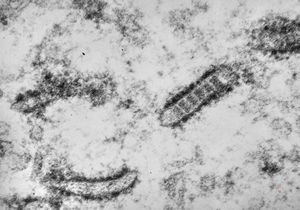

M,21y. | annulate lamellae - intracranial germinoma

M,21y. | annulate lamellae - intracranial germinoma